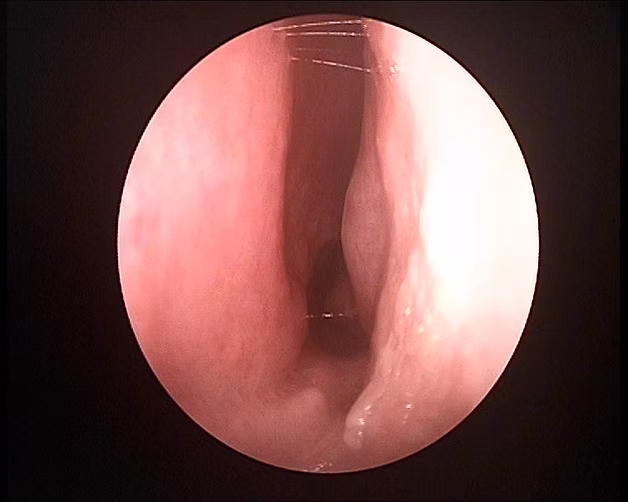

Después de la cirugía

Se observa el tabique nasal y columela en la línea media. El paciente mejora la respiración y elimina el ronquido.